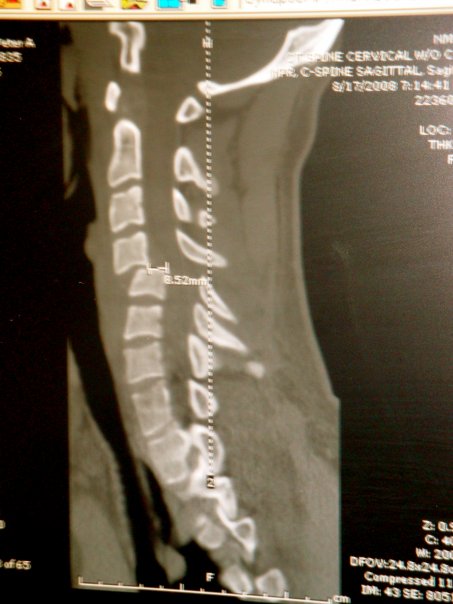

My body continues to grow stronger everyday but my arms are very weak. I cant lift them up or move them. I also have no sense of temperature from the neck down.

this all happened from diving off the back of a friends boat in 4 ft of water. the past 2 weeks i've had alot of ups and downs but my family and friends have been great to me. I have every resource available and all the support i need.

Attached Images